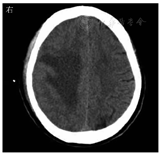

患者男,59岁,因"突发左上肢无力30 h"于2022年3月28日收入丽水市中心医院。患者30 h前在家中无明显诱因下突发左上肢无力,不能持物,伴头晕,无头痛,言语及行走如常,休息无好转,当时未重视,未诊治,症状无缓解。既往有下肢静脉血栓病史,脑动脉瘤手术史;高血压病史多年,氨氯地平片10 mg/次(1次/d)规律服药。入院体格检查:意识清楚,体温为36.8 ℃,脉率为99次/min,呼吸频率为20次/min,血压为170/96 mmHg(1 mmHg=0.133 kPa);双侧瞳孔等大等圆,对光反射灵敏,无眼震,双侧鼻唇沟对称,伸舌居中,左上肢肌力Ⅱ级,左下肢肌力Ⅳ级,右侧肢体肌力正常,四肢肌张力正常,左侧巴宾斯基征(+)。入院当天实验室检查示:白细胞计数为7.1×109/L,中性粒细胞比例为0.763,淋巴细胞比例为0.176,血红蛋白为165 g/L,血小板计数为174×109/L;快速超敏CRP为5.91 mg/L,降钙素原为0.04 μg/L,白蛋白为33.4 g/L,血钙为2.09 mmol/L;血脂、血糖、尿常规、粪便常规未见异常。3月28日头颅MRI检查示右侧额叶见一片状不规则肿块(图1),大小约2.3 cm×1.4 cm×1.8 cm,弥散明显受限,双侧侧脑室旁白质区多发腔隙性脑梗死,部分软化灶;动脉瘤术后;右侧额窦、双侧上颌窦炎症。予氨氯地平片10 mg(1次/d)降压、阿托伐他汀钙片20 mg(1次/d)调脂稳斑等对症治疗。4月1日,患者偶感头晕、头痛,体格检查:左上肢肌力0级,左下肢肌力0级,右侧肢体肌力Ⅴ级,四肢肌张力正常,左侧巴宾斯基征(+);头颅MRI增强检查示右侧额叶占位,团片状病灶增大,约4.5 cm×2.4 cm×2.1 cm。因左侧肢体无力进展较快,考虑脑脓肿,于当天行头颅引流手术,抽出黄色浓稠脓液约15 mL,脓液送细菌涂片及细菌培养检查,涂片检出革兰阴性杆菌和革兰阳性球菌(图2)。脑脓肿诊断明确,予美罗培南针2.0 g/次(每8 h 1次)静脉滴注联合万古霉素针1.0 g/次(每12 h 1次)静脉滴注,以及阿米卡星20 mg/次(1次/d)注入脓肿腔治疗。4月4日,脓液厌氧培养出5种细菌,经质谱鉴定为直肠弯曲菌、具核梭杆菌、微小微单胞菌、牙龈卟啉单胞菌和福赛斯坦纳菌;直肠弯曲菌及厌氧菌的药物敏感试验困难未检测。4月8日,脑脓肿脓液宏基因组学二代测序结果提示直肠弯曲菌(特异序列数为2 826)、具核梭杆菌(特异序列数为59 904)、微小微单胞菌(特异序列数为25 246)、牙龈卟啉单胞菌(特异序列数为8 953)、龈沟产线菌(特异序列数为6 471)、福赛斯坦纳菌(特异序列数为3 673),证实直肠弯曲菌合并多种厌氧菌感染。4月13日,头颅MRI检查示脓肿周围水肿加重,感染科会诊后改用青霉素480万U/次(每6 h 1次)静脉滴注联合氯霉素1.5 g/次(1次/d)静脉滴注治疗脑脓肿,因丽水市中心医院氯霉素缺货,用青霉素480万U/次(每6 h 1次)静脉滴注联合奥硝唑0.5 g/次(每12 h 1次)静脉滴注治疗脑脓肿。2022年4月20日,改用青霉素480万U/次(每6 h 1次)静脉滴注联合氯霉素1.5 g/次(1次/d)静脉滴注治疗脑脓肿。5月8日,患者体温正常,无咳嗽、咳痰,无头痛、呕吐,炎症指标恢复正常,停用抗菌药物,予康复治疗。2022年5月20日,患者住院54 d,脑脓肿经切开引流后抗菌药物治疗38 d,康复治疗2周后能独立站,室内步行,炎症指标正常,病情稳定,予以出院。

直肠弯曲菌是弯曲菌属的一种,微需氧或厌氧生长,革兰染色阴性,弯曲呈弧形、S形或螺旋形杆菌,在陈旧的培养物中或长时间暴露在空气中可形成球形。直肠弯曲菌为口腔定植菌群的一种[1],其较少引起口腔外感染,主要从活动性牙周感染患者中分离,但也有肺部感染的报道[2],亦有在乳腺囊肿患者中分离到该菌的报道[3],但是直肠弯曲菌引起颅内感染的报道非常少[4]。具核梭杆菌为梭杆菌属的一种,是口腔的定植菌群之一,是革兰染色阴性、无芽孢的专性厌氧菌。具核梭杆菌不仅可引起口腔感染性疾病[5],还与大肠癌及脑、肝、肺、脾等脏器感染密切相关[6]。微小微单胞菌为革兰阳性专性厌氧球菌,是口腔的定植菌,是牙周炎主要可疑病原菌之一,其还与腹部脓肿、肝脓肿、心内膜炎、化脓性关节炎、脑膜炎、菌血症、根尖周炎及冠周炎等相关[7,8,9]。牙龈卟啉单胞菌、龈沟产线菌及福赛斯坦纳菌均为口腔定植专性厌氧菌,且为重要的牙周炎致病菌,在牙周疾病的发生和发展中起着重要作用[10,11,12,13]。本例患者为中年男性,既往有下肢静脉血栓病史、动脉瘤术后,本次在家中无明显诱因下突发左上肢无力,不能持物,伴头晕;头颅MRI检查发现右侧额叶见一片状不规则肿块,头颅手术引流抽出黄色浓稠脓液,脓液标本涂片检查见革兰阴性杆菌和革兰阳性球菌,脓液培养检出5种细菌,故细菌性脑脓肿诊断明确。